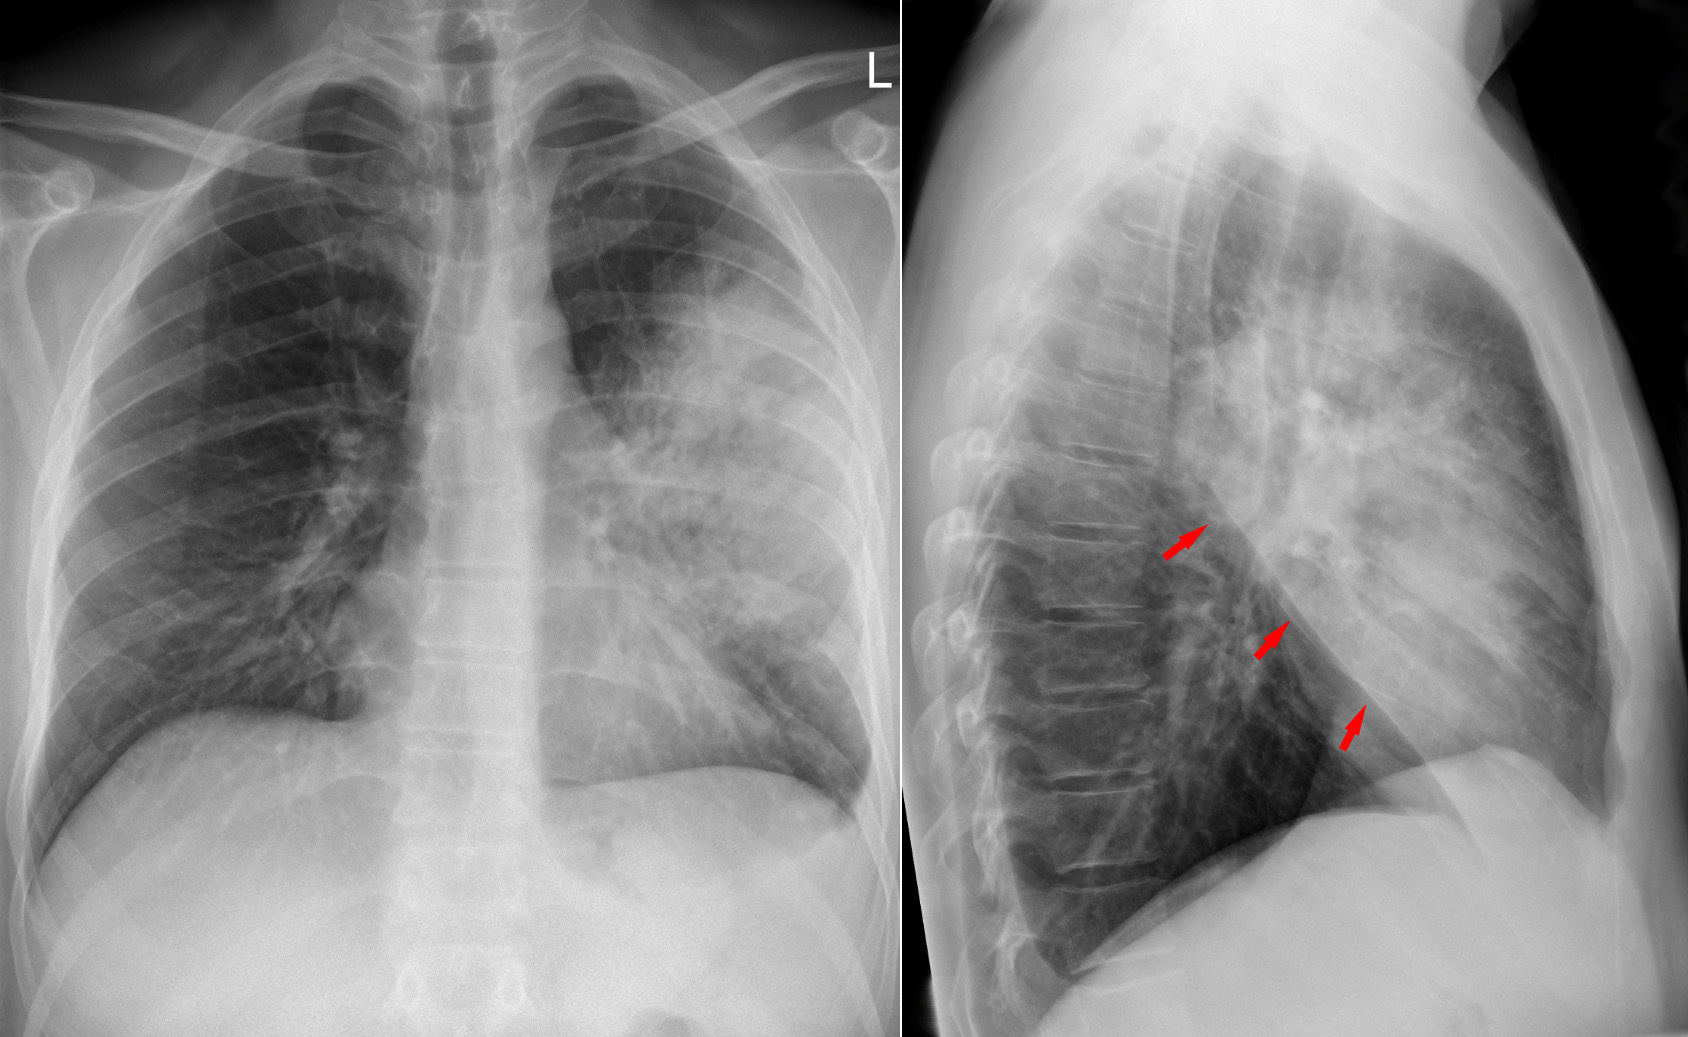

Доктор Сергей Авдеев раскрыл основной фактор риска развития пневмонии, пишет «РИА Новости». У курильщиков вероятность развития заболевания в 4 раза выше.

Фото: commons.wikimedia.org, Hellerhoff, Creative Commons Attribution-Share Alike 3.0 Unported license.